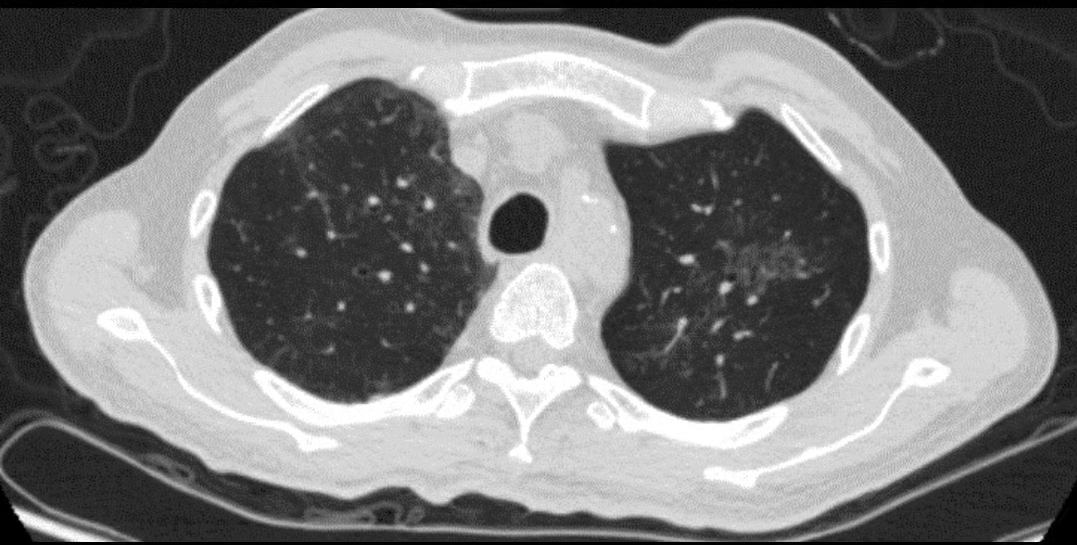

“我以为是普通感冒,便没有太在意。没想到,这个病差点要了我的命......”今年1月初,家住南宁的张大伯突然出现了咳嗽、发热、呼吸困难、咳白色粘痰的症状,一开始以为是普通的受凉感冒,吃了感冒药后症状并没有好转,便前往当地某医院就诊。排除新冠病毒及其他常见的呼吸道病原抗体,经检查,张大伯的肺部CT显示右肺上下叶感染性病变,诊断为肺炎收治入外院。随后几天,张大伯病情迅速恶化,住进外院ICU对症治疗两天,但效果依旧不好,张大伯仍然反复发热,病变较前明显加重。

1月14日晚上,在连续发热的第八天,张大伯辗转来到广西医科大学第一附属医院,以“社区获得性肺炎(重症)I型呼吸衰竭”紧急收住在重症医学科二病区进行治疗。入院时,张大伯体温达39.5℃,心率高达140以上,呼吸快至40次/分,血氧饱和度低至87%,并伴有严重的急性呼吸衰竭。张大伯在入科后立即予经鼻高流量吸氧,但他的氧分压仍无法维持正常,随后重症医学科医生决定对其立即进行气管插管术,并以俯卧位通气改善气血比例及加强痰液引流等治疗。

查明了病因,治疗就有方向了。重症医学科团队立即调整抗生素并对症治疗,经过医护人员的精心治疗和护理,张大伯两肺情况好转,成功撤除ECMO。1月27日,张大伯神志清醒病情平稳,各项指标、脏器功能也都恢复正常,转至普通病房继续治疗。2月9日,张大伯顺利治愈出院。

②由于鹦鹉热衣原体肺炎的非特异性征象,感染早期的鉴别诊断具有挑战,根据临床症状、影像学表现及流行病学史,还需要与流感病毒、真菌等引起的肺部感染相鉴别。